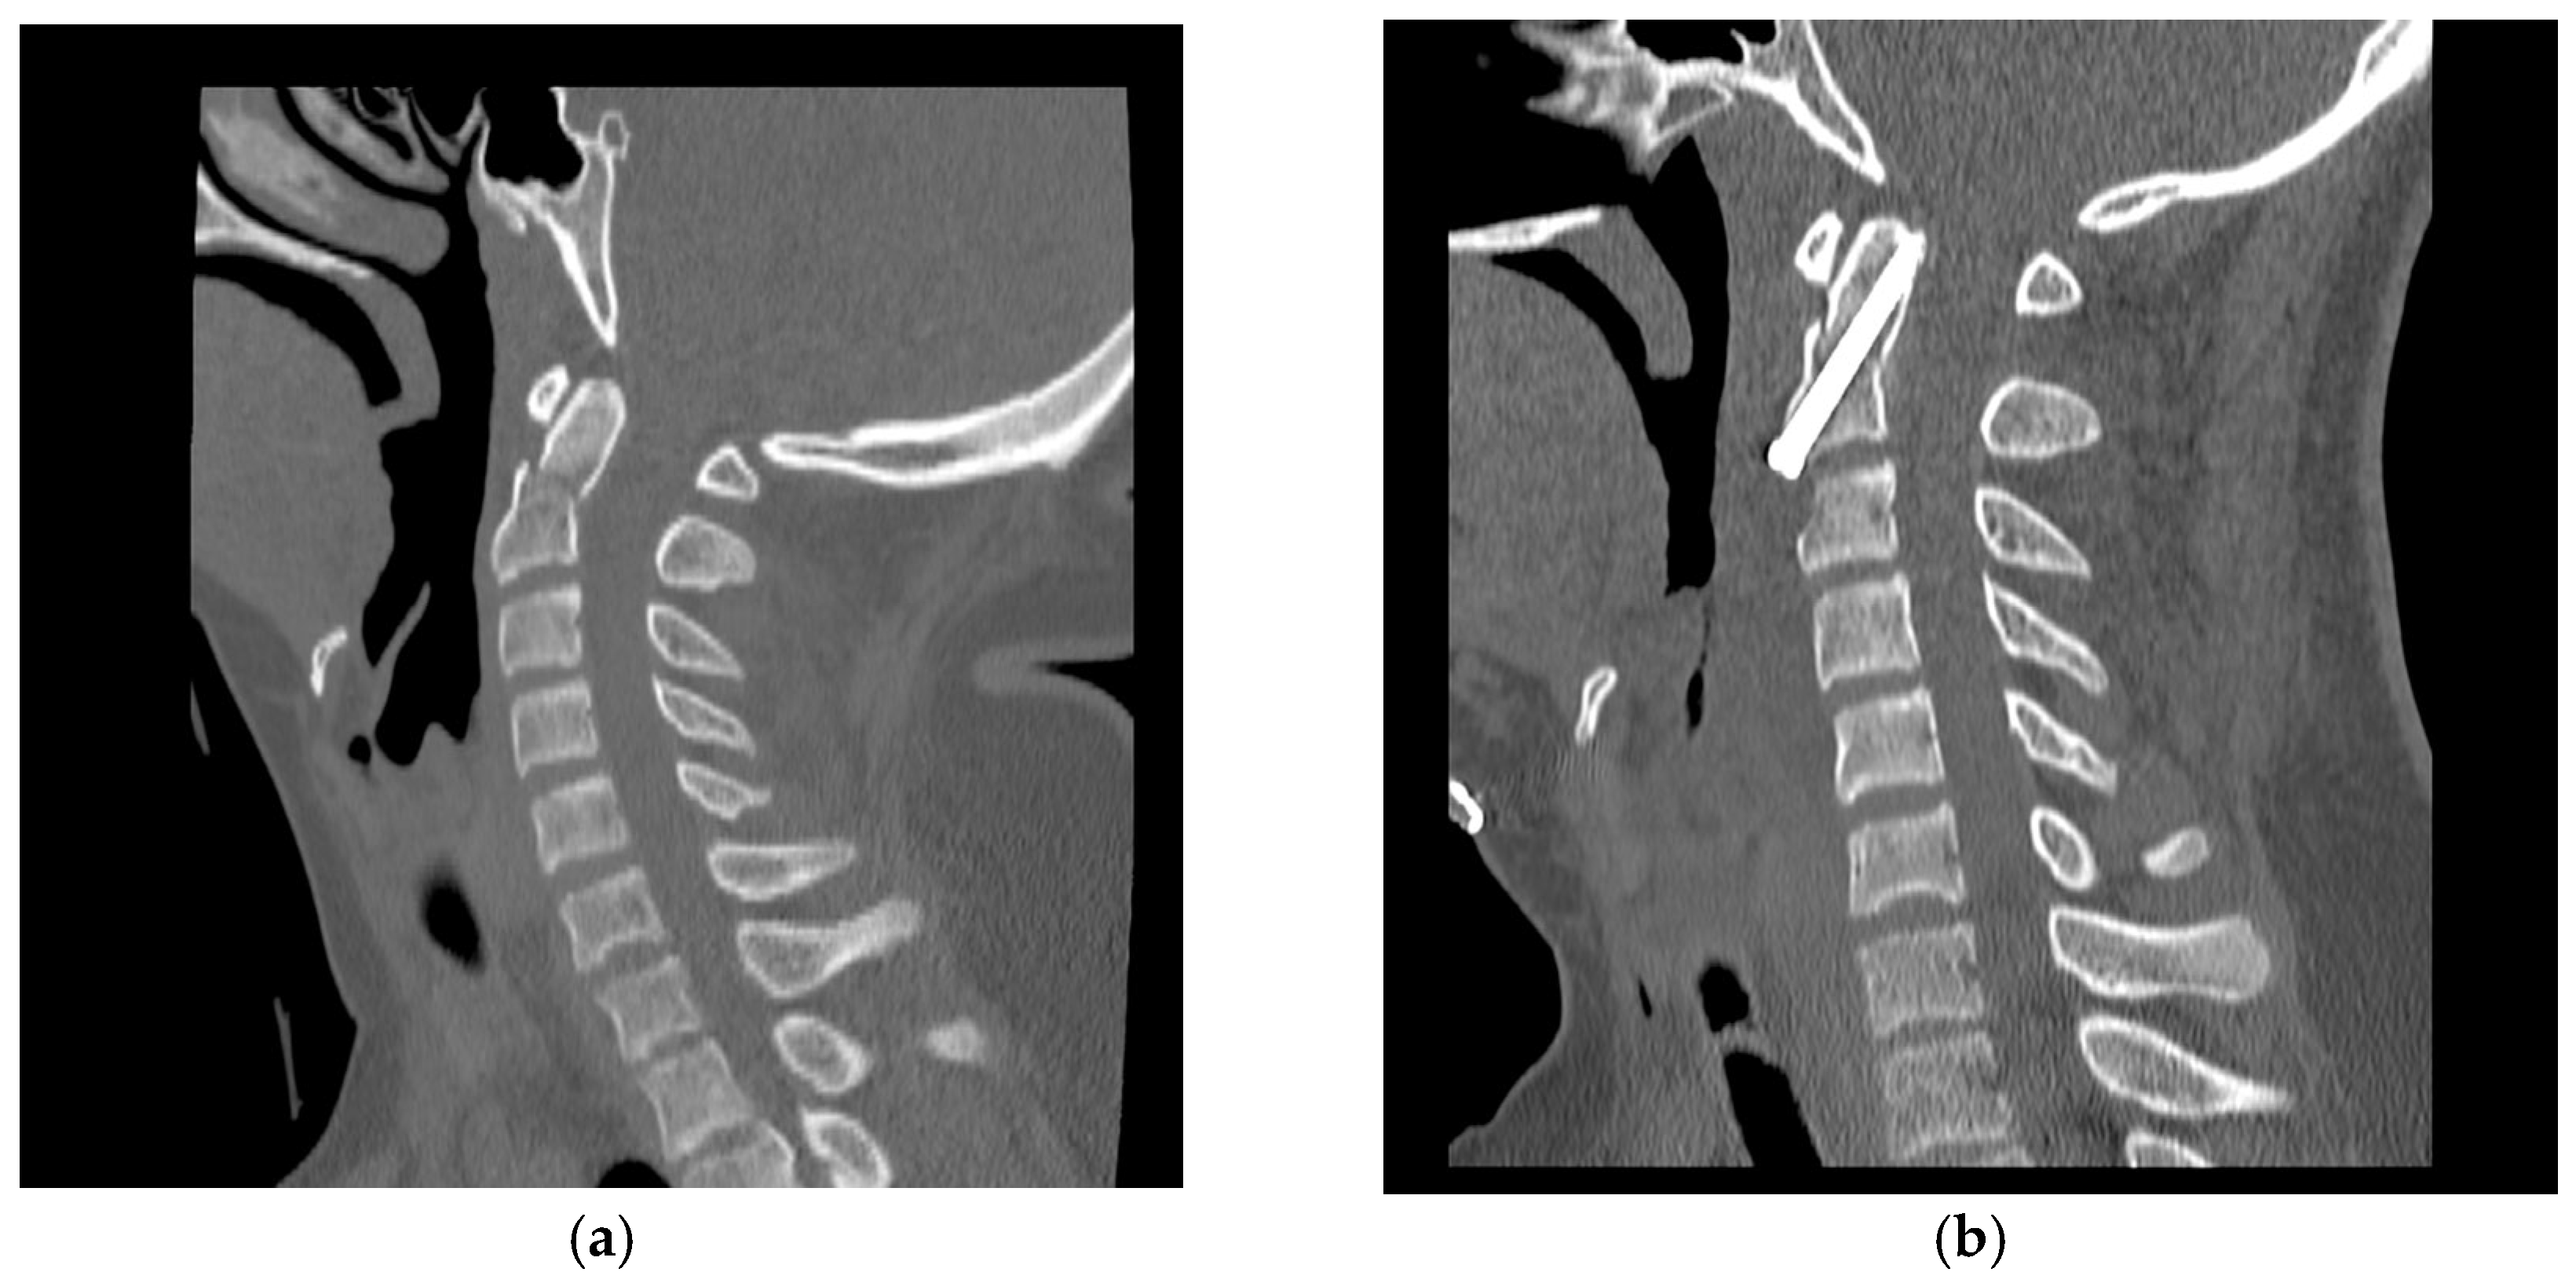

Cervical CT confirmed proper implant positioning and reduction within 24 h in all patients. This is illustrated in Figure 1, which shows preoperative displacement and postoperative alignment restoration. Dynamic radiographs and CT were repeated at 6 weeks, 3 months, and 6 months, with bone fusion primarily documented at 3 months.

Figure 1. Sagittal CT scans of the cervical spine. (a) Preoperative image showing a type II odontoid fracture with displacement and angulation. (b) Postoperative image demonstrating correct placement of the anterior odontoid screw with anatomical reduction and restoration of alignment. Example from a 17-year-old male patient.